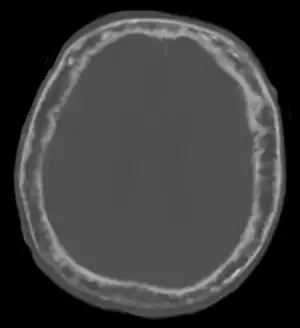

![]() | |

| "This 92 year-old male patient presented for assessment of sudden inability to move half his body. An incidental finding was marked thickening of the calvarium. The diploic space is widened and there are ill-defined sclerotic and lucent areas throughout. The cortex is thickened and irregular. The findings probably correspond to the 'cotton wool spots' seen on plain films in the later stages of Paget’s disease." | |

Paget's disease affecting the skull may cause frontal bossing, increased hat size, and headaches. Often patients may develop loss of hearing in one or both ears[6] due to auditory foramen narrowing and resultant compression of the nerves in the inner ear. Rarely, skull involvement may lead to compression of the nerves that supply the eye, leading to vision loss.[6]